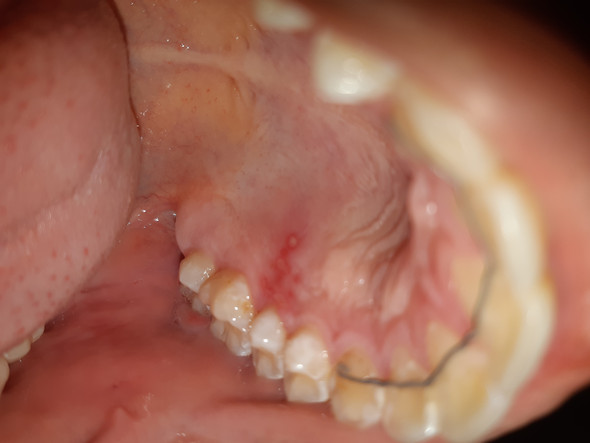

Hallo erst mal wieder mal schlaflos in Fürstenfeldfolgende Fragehabe seit zwei Wochen einen roten Fleck am harten Gaumenfast ne Gaumenhälfte grosswenn ich mit der Zunge drüberfahre ist die Stelle schmerzlosglatt und es fühlt sich so an als ob der Fleck rundherum eingerenzt wärwar beim zahnarztder hat mich zur hautärztin geschicktund die hat mir. Rote Flecken am Gaumen können verschiedene Ursachen haben. Der fleck fühlt sich glatter an als der Rest vom Gaumen ich war auch schon bei meiner Ärztin und sie meinte es wäre eine Verbrennung aber so lange bleibt doch keine verbrennung zu sehen.

Anfang August einen roten Fleck am gaumen der nicht weh tut immer noch gleich aussieht und ich auch keinerlei andere Symptome habe. Machen Sie jetzt den Test und beantworten Sie folgende 10 Fragen. Hallo seit knapp einer Woche habe ich eine geschwollene Stelle am Gaumen.

Manche dieser Flecken sind zwar störend aber harmlos während andere ein Zeichen für ein ernsteres gesundheitliches Problem sein können das genauer untersucht werden muss. Weiße Stellen können auch durch Wangenbeißen oder durch Reiben der Wangen oder Zunge auf einem scharfen Teil eines Zahns oder einer Zahnfüllung.

Der fleck fühlt sich glatter an als der Rest vom Gaumen ich war auch schon bei meiner Ärztin und sie meinte es wäre eine Verbrennung aber so lange bleibt doch keine verbrennung zu sehen. Oft handelt es sich um Nahrungsreste die sich wegwischen lassen. La syntaxe dans laquelle sont dé crites entre autres les différences entre da et veil WT 1978-D est une syntaxe indépendante du contexte. überall im Mund auftreten. Die anderen Stellen im Mund sind auch gut verheilt es ist nun jedoch noch ein kleiner 2mm roter Fleck direkt oben am Gaumen dieser ist nicht erhaben und befindet sich dort wo die kleine Verletzung war. Mundbedingungen die eine Veränderung der Farbe verursachen können eventuell ein Problem widerspiegelnWeiße Flecken können z. Roter Fleck am Gaumen.